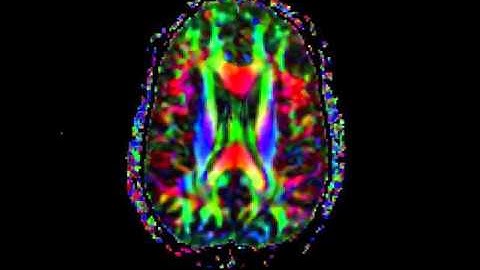

Diffusion Tensor Tractography DTI MRI 5 - William Edward Hahn